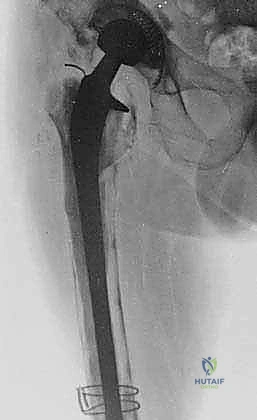

- الأشعة السينية الرقمية (Digital X-rays): لتقييم وضع المفصل الحالي، وتحديد مقدار العظم المفقود، وتصنيف حالة العظم.

الخطوات الجراحية: كيف تتم عملية استبدال الجزء العلوي من الفخذ؟

هذه الجراحة هي بمثابة عمل هندسي دقيق داخل جسم الإنسان. بفضل استخدام تقنيات الجراحة الميكروسكوبية وخبرته الطويلة، ينفذ الأستاذ الدكتور محمد هطيف هذه العملية عبر خطوات مدروسة ومحكمة:

5. تجميع وزراعة المفصل المعياري (Modular Prosthesis Implantation)

هنا تتجلى روعة التكنولوجيا الطبية الحديثة. بدلاً من مفصل بقطعة واحدة، يستخدم الدكتور هطيف "مفصل معياري" يشبه قطع تركيب (Lego). يتكون من:

* الجذع السفلي (Distal Stem): يتم تثبيته في العظم السليم المتبقي في منتصف أو أسفل الفخذ (غالباً بدون أسمنت عبر النمو العظمي، أو باستخدام الأسمنت حسب حالة العظم).

* الجسم (Body/Segment): قطع معدنية أسطوانية بأطوال مختلفة لتعويض العظم المفقود بدقة واستعادة طول الساق الطبيعي.

* العنق والرأس (Neck and Head): يتم اختيار الزاوية والطول المناسبين لضمان استقرار المفصل وتوتر العضلات.

يتم تجميع هذه القطع وتثبيتها ميكانيكياً بقوة هائلة داخل غرفة العمليات لتشكيل عظم فخذ اصطناعي كامل.

![الأشعة السينية بعد العملية](/media/huta